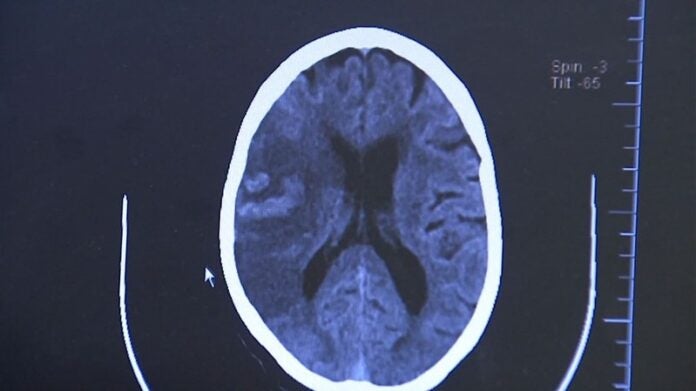

Diagnóstico e reabilitação

O diagnóstico é feito por tomografia computadorizada ou ressonância magnética do crânio. “Esses exames permitem detectar a área afetada e definir se é um AVC isquêmico ou hemorrágico”, diz Chaddad.